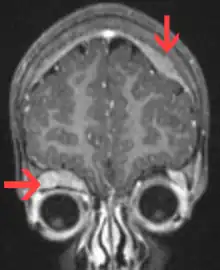

On microscopy, the tumor cells are typically described as small, round and blue, and rosette patterns (Homer Wright pseudorosettes) may be seen. Homer Wright pseudorosettes are tumor cells around the neuropil, not to be confused with a true rosettes, which are tumor cells around an empty lumen.[27] They are also distinct from the pseudorosettes of an ependymoma which consist of tumor cells with glial fibrillary acidic protein (GFAP)–positive processes tapering off toward a blood vessel (thus a combination of the two).[28] A variety of immunohistochemical stains are used by pathologists to distinguish neuroblastomas from histological mimics, such as rhabdomyosarcoma, Ewing's sarcoma, lymphoma and Wilms' tumor.[29]